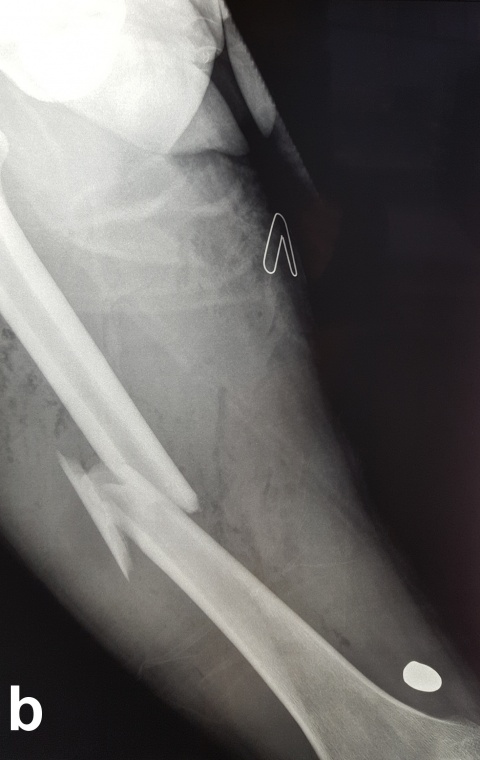

Beim Auftreffen des Projektils im Rahmen von Niedrigenergieverletzungen auf Knochengewebe entsteht meist eine typische, einfache Fraktur (Abbildung 2). Hochenergieverletzungen des Knochens münden in eine multifragmentäre Situation, bei der ein Großteil der Projektilenergie an den Knochen abgegeben wird. Insbesondere lange Röhrenknochen können, da sie wie eine starre, spröde flüssigkeitsgefüllte Röhre agieren, durch Projektile mit hoher Energie explosionsartig zerstört werden (Abbildung. 3).

Insbesondere bei Schussfrakturen verursacht durch Hochenergieprojektile ist neben ausgeprägten Weichteilverletzungen mit einer massiven Trümmerzone aus avitalen Knochenfragmenten zu rechnen. In diesen Fällen muss ein radikales Débridement sowohl der avitalen Weichteile, aber auch der avitalen Knochenfragmente erfolgen [1]. Aufgrund der hohen Kontaminationsrate durch in den Schusskanal gezogene Kleidungsreste und Fremdkörper mit entsprechend erhöhtem Infektionsrisiko [21, 43], ist die primäre Stabilisierung durch einen Fixateur externe das Mittel der Wahl [1]. Dies gilt insbesondere dann, wenn nicht eindeutig ist, ob um eine Niedrig- oder Hochenergieverletzung vorliegt. Dieses Vorgehen wird durch die Publikation von Long et al. [44] unterstützt. In dieser Arbeit bezüglich der Schussverletzungen am Femur wurde anhand von klinischen und radiologischen Befunden eine Einteilung in 3 Schweregrade vorgenommen. Während Grad-1-Verletzungen Niedrigenergieverletzungen waren, die allesamt primär mit einem Marknagel versorgt wurden, wiesen Grad-2- und Grad-3-Verletzungen Zeichen einer Hochenergieverletzung auf. Diese Patienten entwickelten im Verlauf in bis zu 50 % der Fälle eine tiefe Wundinfektion, was eindeutig gegen eine primäre osteosynthetische Ausversorgung spricht. Zudem waren bei Verletzungen der Grade 2 und 3 auch wiederholte Débridements notwendig.

der Schussfraktur des rechten Femurs zudem das noch oberhalb des Kniegelenks befindliche Projektil.

c: Klinisch bestehen ein Ein- und Ausschuss am linken Oberschenkel (rechter Bildrand) mit isolierter und unkomplizierter Weichteilverletzung sowie ein isolierter Einschuss am rechten Oberschenkel medial ohne dazugehörigen Ausschuss. Es wurde nur ein Schuss abgegeben.